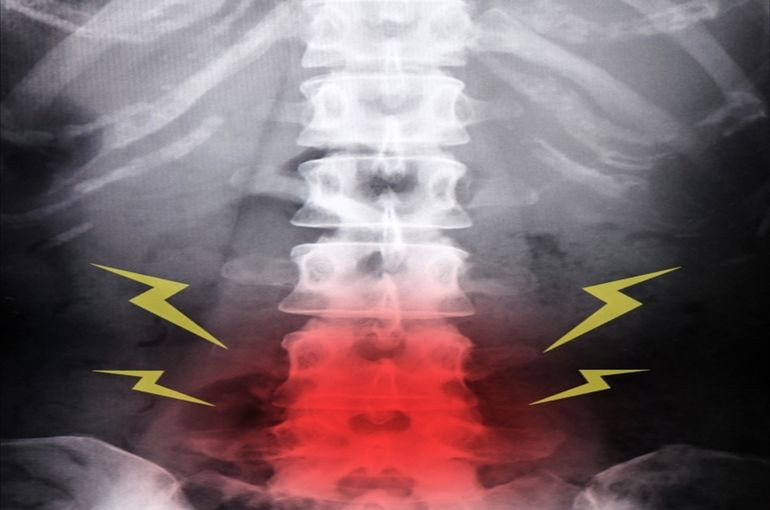

「腰痛」

です。

「夏場の腰痛」

について説明していきます。